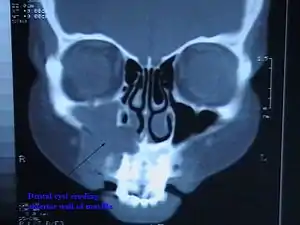

CT scan through head showing a right periapical cyst

Most frequently located in the maxillary anterior region, the cyst is caused by pulpal necrosis secondary to dental caries or trauma. Its lining is derived from the epithelial cell rests of Malassez which proliferate to form the cyst.[2] Such cysts are very common. Although initially asymptomatic, they are clinically significant because secondary infection can cause pain and damage. In radiographs, the cyst appears as a radiolucency (dark area) around the apex of a tooth's root.[3]

Several lesions can appear similarly in radiographic appearance.[2] Intraoral X-rays or a 3-D cone beam scan of the affected area can be used to obtain radiological images and confirm diagnosis of cysts in the periapical area. Circular or ovoid radiolucency surrounding the root tip of approximately 1-1.5 cm in diameter is indicative of the presence of a periapical cyst.[2] The border of the cyst is seen as a narrow opaque margin contiguous with the lamina dura. In cysts that are actively enlarging, peripheral areas of the margin may not be present. Periapical cysts have a characteristic unilocular[8] shape on radiographs. There is also a severe border of cortication[9] between the cyst and surrounding bone. Pseudocysts, on the other hand, have a fluid filled cavity but are not lined by epithelium, therefore they have a less severe and more blurred border between the fluid and bony surroundings.[10]